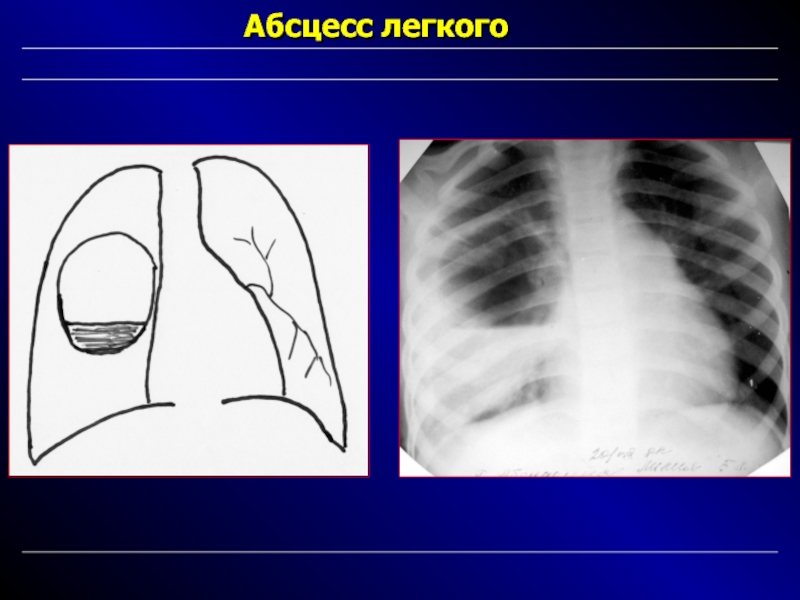

Бактериальная деструкция легких у детей презентация - 88 фото